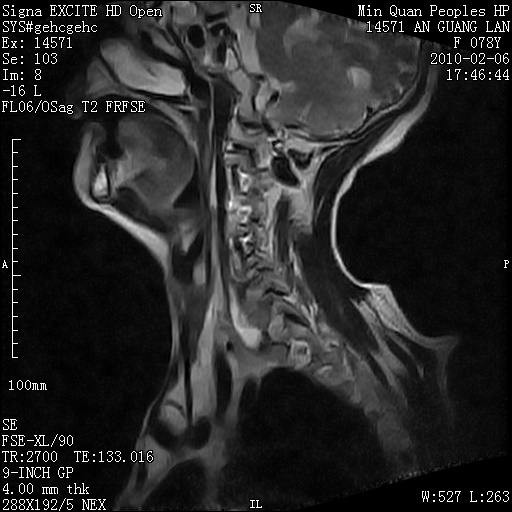

标题: MRI2763:C6、C7椎体病变性质?

f,78y,颈部与双上肢阵发性剧痛40余天。ct可见c6、c7椎体虫蚀样破坏,其间椎间隙变窄(没有图片资料可供上传)。

考虑椎体结核并椎旁脓肿。

考虑:c6/7椎体结核并椎旁脓肿形成,建议增强扫描。